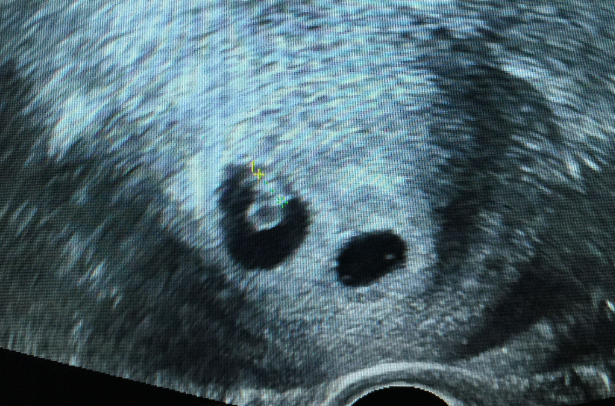

试管婴儿技术的实施过程包括以下几个步骤:首先是促排卵,通过使用人工促排卵药物来刺激卵巢排出多个卵子;然后是取卵,在卵巢发育到一定程度后,通过穿刺抽取卵子;接下来是将卵子和精子在实验室中受精,形成胚胎;最后是将胚胎移植到子宫中,等待着胚胎着床并发育。